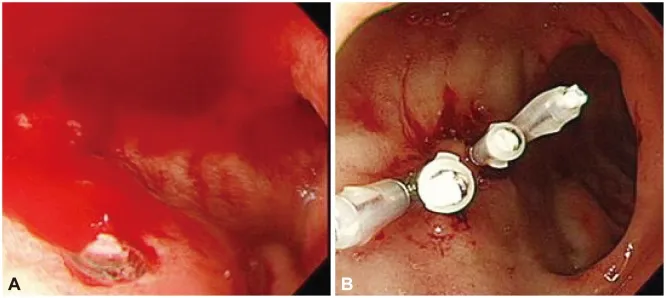

Managing follows a treat-to-target strategy, with mucosal healing as the therapeutic endpoint reducing long-term complications by 50%. NICE NG129 recommends starting moderate-to-severe Crohn's with corticosteroids (prednisolone 40 mg daily, taper over 8 weeks) plus azathioprine 2-2.5 mg/kg for maintenance. Failure to achieve remission by 12 weeks mandates biologics: infliximab 5 mg/kg at weeks 0, 2, 6, then 8-weekly. For , endoscopic haemostasis (adrenaline injection plus thermal coagulation) achieves initial control in 90% of cases, but rebleeding occurs in 10-20%-requiring repeat endoscopy or interventional radiology.